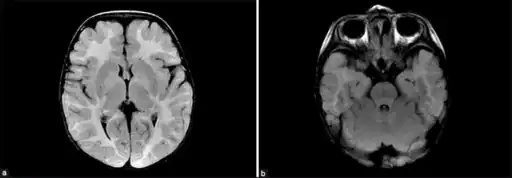

SUCLA2 and RRM2B related forms result in deformities to the brain.[5] A 2007 study based on 12 cases from the Faroe Islands (where there is a relatively high incidence due to a founder effect) suggested that the outcome is often poor with early lethality.[17] More recent studies (2015) with 50 people with SUCLA2 mutations, with range of 16 different mutations, show a high variability in outcomes with a number of people surviving into adulthood (median survival was 20 years). There is significant evidence (p = 0.020) that people with missense mutations have longer survival rates, which might mean that some of the resulting protein has some residual enzyme activity.[2]